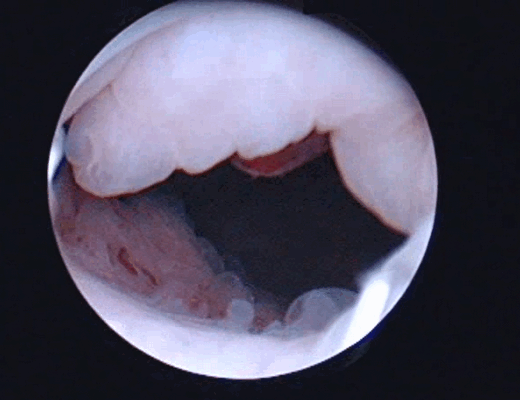

Цистоскопическое обследование пациента М.

Цистоскопическая картина солидного образования, вдающегося в полость мочевого пузыря в виде массивных бугристых масс, покрытых отечной слизистой оболочкой с очагами кровоизлияний, с явлениями распада и инкрустации солями

По данным ультрасонографии ретенционные изменения верхних мочевых путей с обеих сторон были выявлены у пациентки О., 35 лет, (чашечки и лоханка справа 16 и 32 мм, слева – 15 и 35 мм соответственно, у остальных пиелокаликоэктазии не было. Больным была выполнена цистоскопия, по данным которой в 3 случаях определялось стелящееся солидное образование в диаметре около 8 см (пациентка О., 35 лет), 5,6 (пациент М., 43 лет) и 2,8 см (пациент С., 56 лет) с явлениями буллезного отека, распада, кровоизлияний и инкрустацией мочевыми солями Образования предположительно характеризовались инфильтративным характером роста.